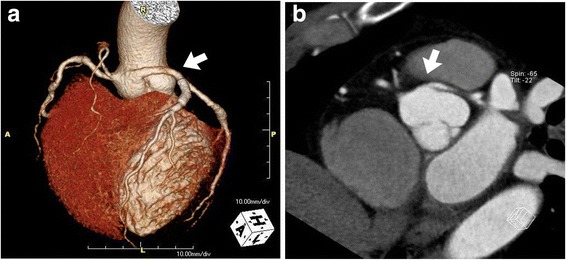

Fig. 2.

a Computed tomography coronary angiography revealed anomalous origin of the left coronary arteries from the right coronary cusp (arrow) in three-dimensional reconstructed image. b Computed tomography coronary angiography showed the anomalous origin of left coronary artery and traveling behind the pulmonary artery (arrow)